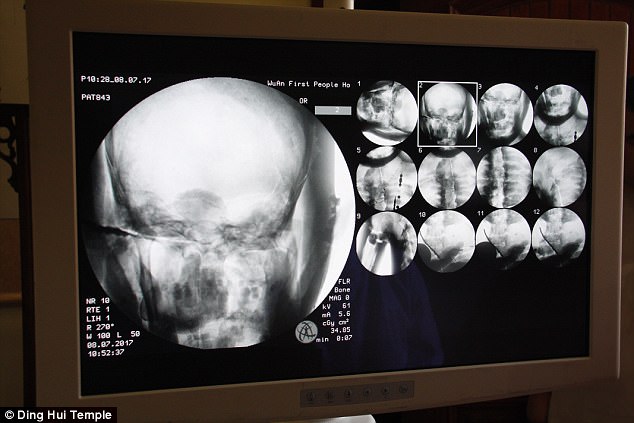

Sự kiện gây chấn động diễn ra vào ngày 8 tháng 7 năm 2017, khi các nhà khoa học tiến hành chụp CT để kiểm tra bên trong "bức tượng" này trước sự chứng kiến của giới truyền thông và đông đảo người dân. Kết quả hình ảnh quét được đã khiến tất cả những người có mặt phải bàng hoàng. Các bác sĩ xác nhận rằng bên dưới lớp mạ vàng, nhà sư Ci Xian vẫn giữ được bộ xương nguyên vẹn cùng một bộ não hoàn chỉnh.

Kết quả hình ảnh từ máy quét đã khiến toàn bộ giới khoa học và những người chứng kiến phải kinh ngạc đến mức sững sờ. Các bác sĩ xác nhận rằng nhà sư Ci Xian vẫn còn giữ được một bộ xương hoàn chỉnh cùng một bộ não nguyên vẹn.

Bác sĩ Wu Yongqing, người trực tiếp tham gia buổi kiểm tra cho biết xương của ngài khỏe mạnh và rõ ràng như một người bình thường. Từ xương hàm trên, răng, xương sườn, xương sống cho đến tất cả các khớp đều vẫn còn nguyên vẹn một cách khó tin. Sự tồn tại hoàn hảo của thi hài sau hơn 1.000 năm đã chứng minh kỹ thuật ướp xác đỉnh cao thời bấy giờ, tạo nên một hiện tượng chấn động khiến cả thế giới phải chú ý.

Những hình ảnh có được sau khi chụp CT